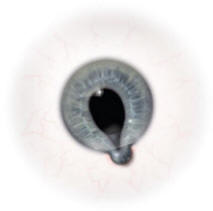

Figure 1. Iris prolapse during cataract

surgery.